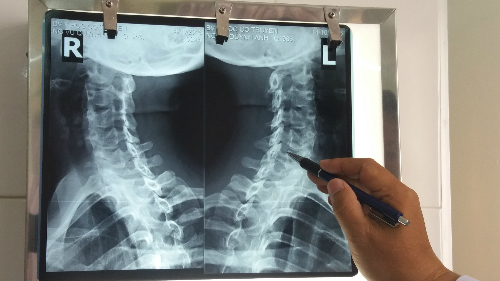

Phim X-quang một bệnh nhân thoái hóa đốt sống cổ. Ảnh: Hoài Nhơn.